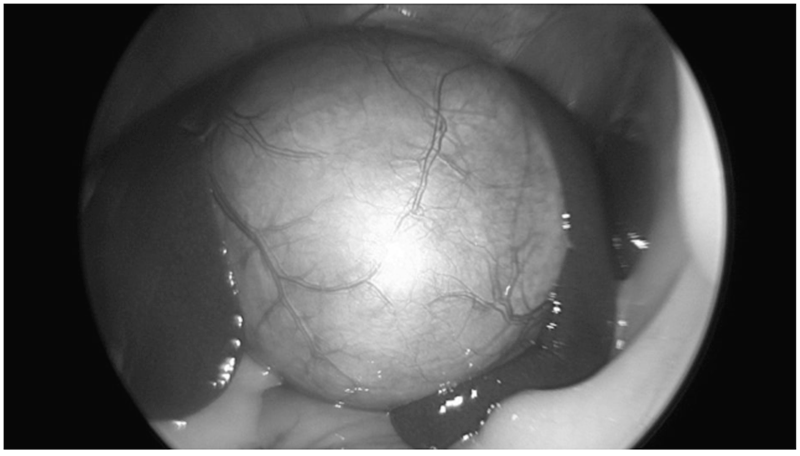

(복강경으로 확인한 노노의 담낭 모습. 굉장히 팽창되어 있는 모습 ▲)

사진에서 표현이 되진 않지만, 담낭이 많이 팽창되어 있어 수술기구로 담낭을 붙잡을 수 없는 상태였고, 그래서 담낭관을 우선 분리하는 기존 방식과 다르게 담낭을 간에서 먼저 분리하는 (Fundus-first) 방식으로 수술을 진행했습니다.)